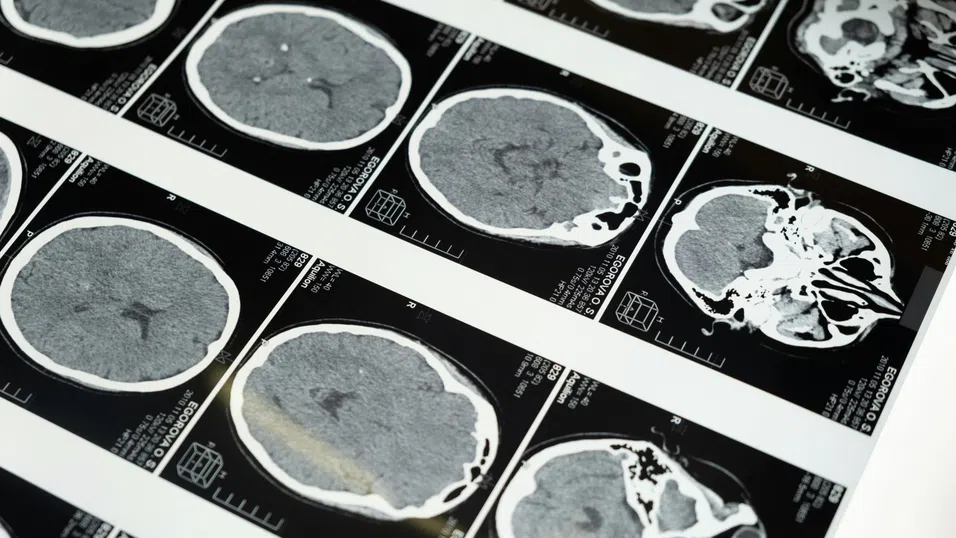

Екипът имплантира микроелектроди в моторната кора – зоната на мозъка, която контролира речта – на четирима участници. Те са помолени или да се опитат да произнесат някои определени думи, или само да си ги представят. И в двата случая мозъчната активност е сходна, което позволява на учените да обучат AI да разпознава и „превежда“ мислени думи в текст.